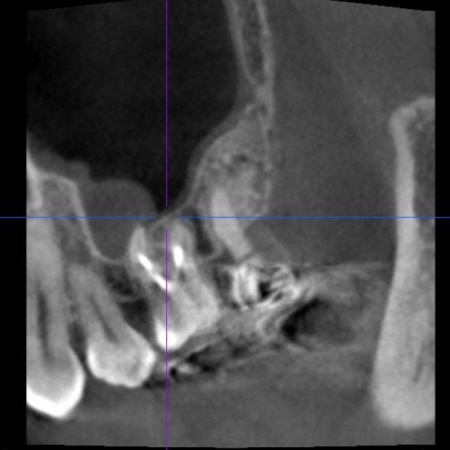

口腔内を拝見し、レントゲンとCT撮影による詳しい検査を行った結果、左上奥歯の歯根内に細菌感染が起きており、炎症が歯根の先から鼻の横にある空洞「上顎洞(じょうがくどう)」にまで広がっていることがわかりました。

これは、歯性上顎洞炎(しせいじょうがくどうえん)と呼ばれる病気で、鼻づまりや鼻水、膿のにおいがするなどの症状があらわれることがあります。

以上のことから、細菌に感染した部位を取り除き、歯の温存を目指す治療が必要だと診断しました。